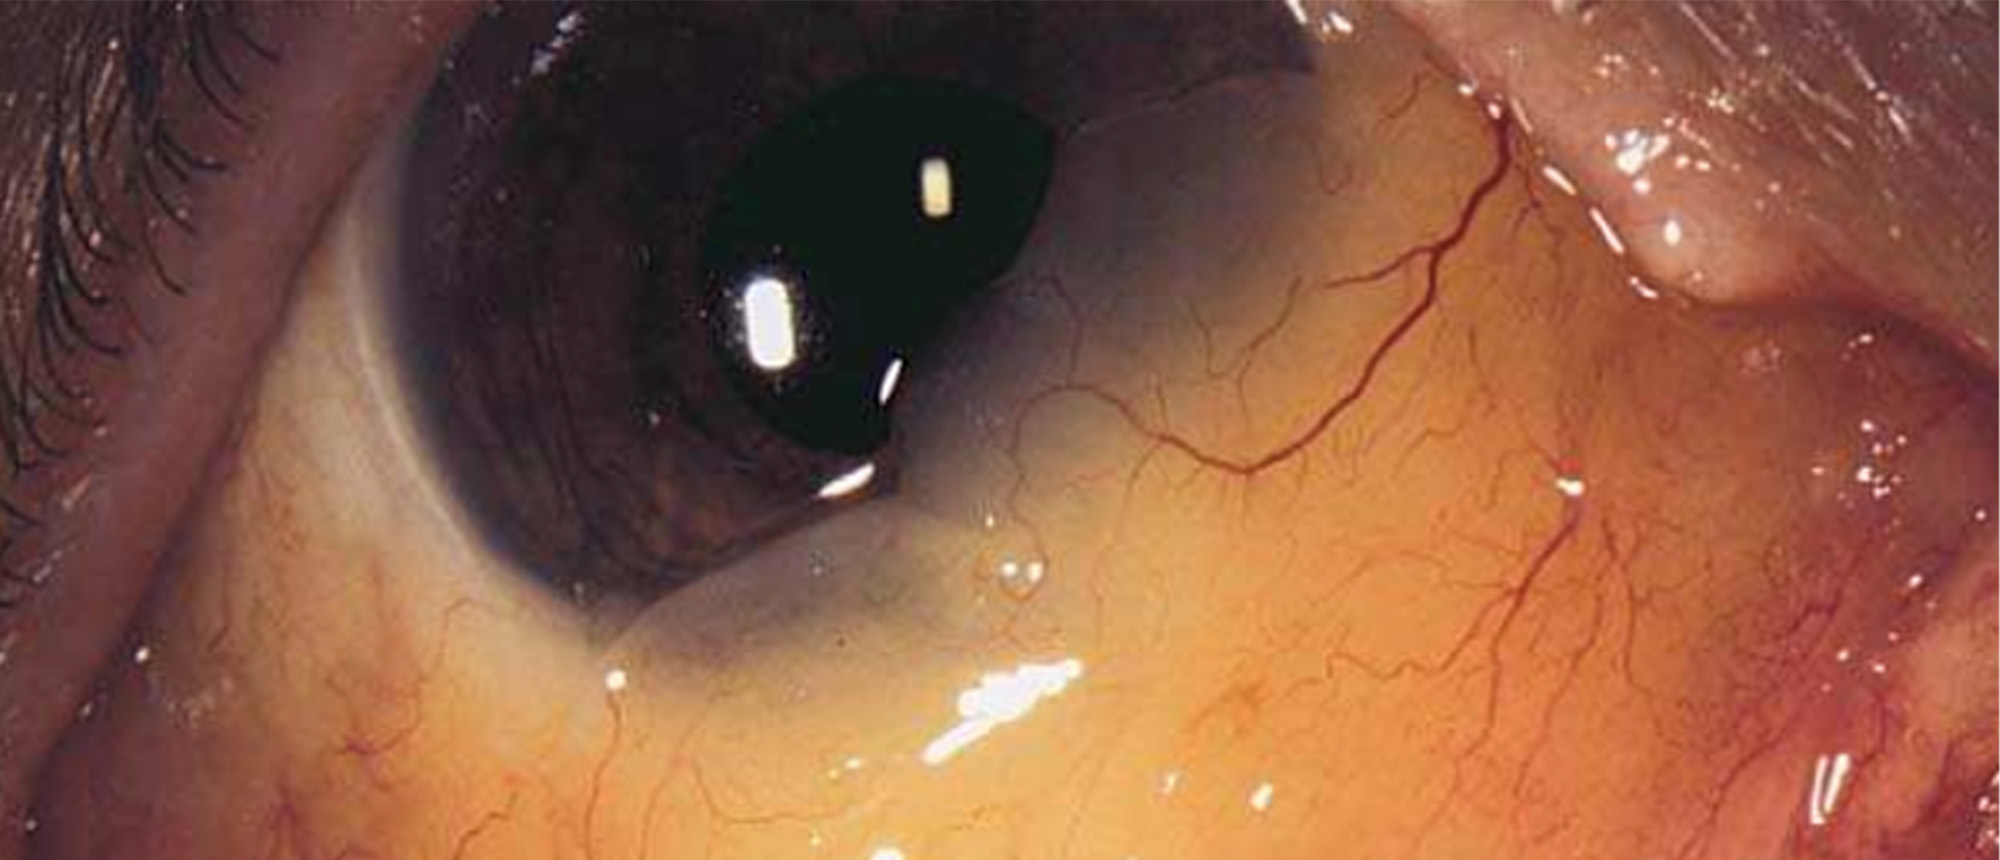

Fusarium Keratitis A patient with no pertinent ocular history presented with 3 months of pain, redness, and blurred vision in the right eye. Visual acuity was HM and slit lamp exam was remarkable for a central infiltrate with feathery irregular margins, significant injection, and a small hypopyon. …